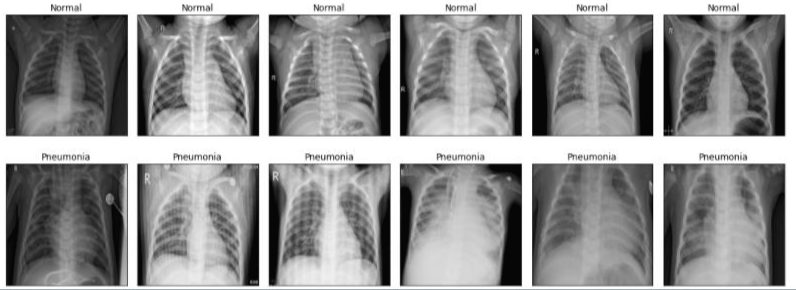

- X-ray 사진에서 혼탁 현상이 없으면 정상이고 있으면 폐렴이다.

4-2) 훈련용 x-ray 사진을 폐렴과 정상으로 분류하여 시각화

- 정상인 x-ray 사진과 폐렴인 x-ray 사진을 분류하여 시각화하였다.

- subplots를 사용하여 1행 6 열인 grid 형태로 만들고 xticks와 yticks를 이용하여 사이 간격을 주었다.

- 반복문이 2개인 이유는 정상 x-ray와 폐렴 x-ray를 따로 반복문을 돌려서 출력했기 때문이다.